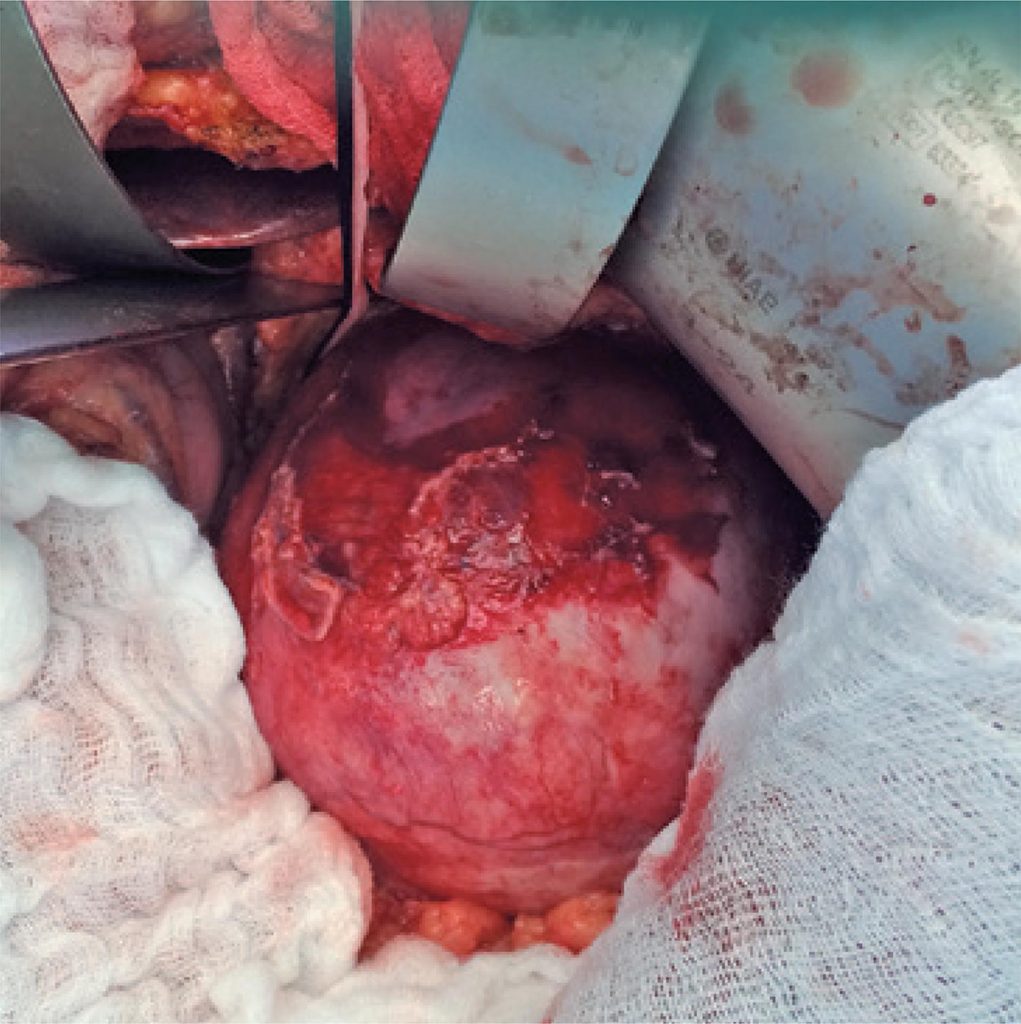

Giant splenic artery aneurysm is a rare condition that represents an eminent life threatening for the patient, requiring, therefore, urgent surgical correction. A 61-year-old woman, former smoker, hypertensive, hypercholesterolemic and multipara sought our service because of a large tumor in the mesogastrium, which was an abdominal ultrasound finding. Despite the size of the tumor, the patient was asymptomatic. The angiotomography and the magnetic resonance image of the abdomen were suggestive of giant splenic artery aneurysm with more than 10cm in diameter that was confirmed by an angiography. She underwent surgery, open splenectomy, and partial aneurysmectomy. The approach of the celiac artery, which was ligated, was only possible with medialvisceral rotation because there was no possibility to view it through the anterior access. The histopathological test of aneurysmatic wall revealed atheroma plaques in the intima. The patient progressed without complications and she was discharged cured. In general, giant splenic artery aneurysms are symptomatic, however, as in the case we report, it may be asymptomatic and found in abdominal imaging exam. Although less invasive Interventional methods exist, such as laparoscopy and endovascular techniques, they were considered inappropriate in this case. Conventional open surgery should be the therapy of choice for a giant splenic artery aneurysm.